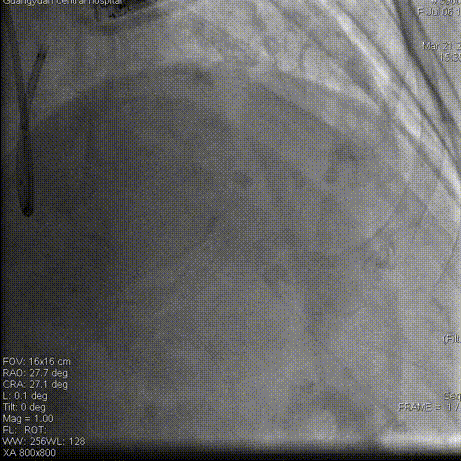

术毕影像

PCI术后结果及随访

即刻结果:提高手术安全性,提高手术效率。该款导引延长导管在此次使用过程中未发生器械不良事件。